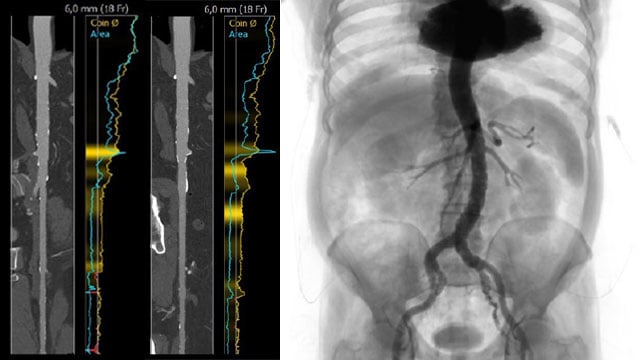

A challenging valve-in-valve scenario in a patient with prior aortic coarctation repair

16 Feb 2026

A 79-year-old with a degenerated aortic bioprosthesis after complex coarctation surgery challenges conventional strategies. Which access route would you choose?